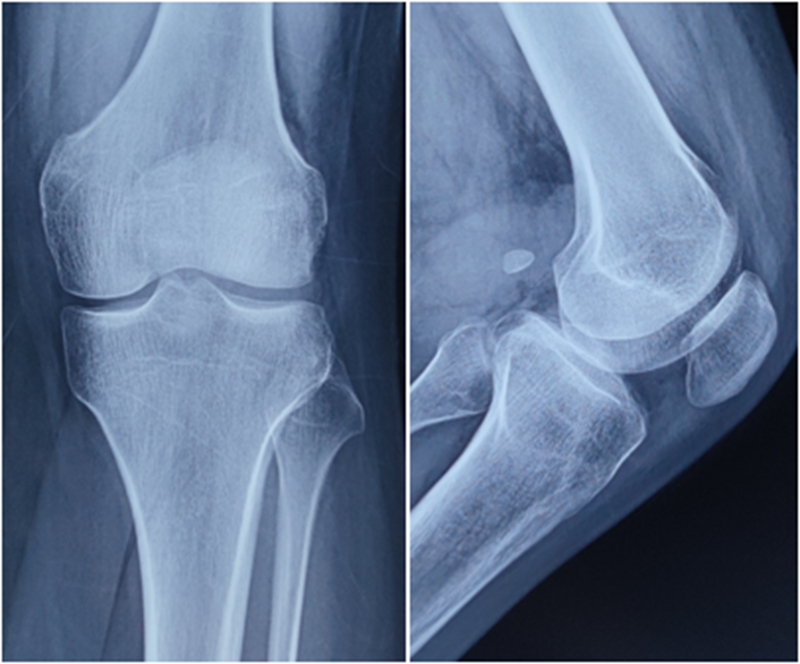

术前X线

术后X线